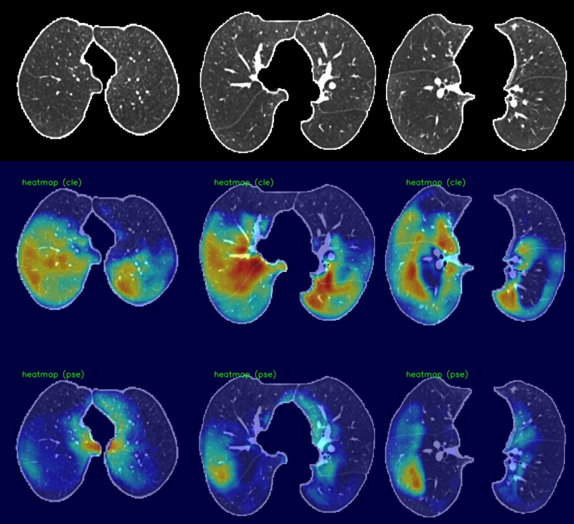

Case I: Confluence in centrilobular, Absent in Paraseptal Emphysema.

Refer to caption

(a) Class Activation Maps. Predicted Advanced for centrilobular, Substantial for Paraseptal.

(b) Regression Activation Maps. Predicted Advanced for centrilobular, Mild for Paraseptal.

Case II: Advanced in centrilobular, Substantial in Paraseptal Emphysema.

(a) Class Activation Maps. Predicted Advanced for centrilobular, Absent for Paraseptal.

Figure 3: Dense class activation maps (left) versus dense regression activation maps (right), We show two cases, and each consists of three rows. The first row shows the input image (cropped and masked by the lung segmentation), the second row illustrates the activation maps for the centrilobular emphysema, and the third row shows the activation maps for the paraseptal emphysema.

We utilized dense activation maps to visualize the features that correspond to the classification decisions. As shown in Figure 3, we present the dense class and regression activation maps on two examples of predicting centrilobular and paraseptal emphysema subtypes. Each example consists of two images, with 3×3333\times 3 tiles, where the left image displays the dense class activation maps and the right image displays the dense regression activation maps. The three columns in each image are sampled axial slices from the input CT scan. For each image, the rows represent the preprocessed input CT scan, the activation map for centrilobular emphysema, and the activation map corresponding to paraseptal emphysema.

In general, the dense class activation maps do not necessarily align with object contours, e.g., blobs of paraseptal emphysema in the second case (Fig. 3 Case II (a)). Naturally, class activation maps only reflect discriminative regions responsible for classification. By utilizing the reconstruction network to generate dense features, our network’s dense class activation maps already provide improved localization compared to the class activation maps generated by the Fleischer algorithm (which tend to be blurry blobs, as seen in their publication). The application of regression training further improves lesion localization, as can be seen in the subpleural paraseptal emphysema in the second case (Figure 3, Case II(b)) and small blobs following the secondary lobular structures in the first case (Figure 3, Case I(b)). Additionally, due to the use of the overlapping loss (Eq.2), the centrilobular and paraseptal activations do not overlap in the dense regression activation maps (Figure3, Case II(b)), unlike in the class activation maps. For instance, in the first case, both class activation maps responded to the same regions in the right lobe (Figure 3, Case I(a)). This highlights the effectiveness of our proposed method in providing improved lesion localization compared to the Fleischer algorithm.